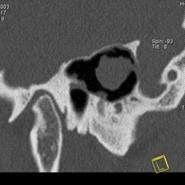

намного сокращается. Например, КТ легких проводится за 20-30 секунд. Рис. 6 на

примере исследования пирамиды височной кости иллюстрирует принцип копьютерной

томографии высокого разрешения. Применены тонкие срезы (0.5 мм) и

"острый" алгоритм реконструкции (кернель 90). (Слева) отчетливо видны

элементы внутреннего уха - улитка, полукружные канальцы. (В центре) показана

проекция продольного сечения височно-нижнечелюстного сустава. (Справа) -

холестеатома.

Рисунок6 -Принципы компьютерной

томографии высокого разрешения (КТВР) на примере исследования пирамиды височной

кости.